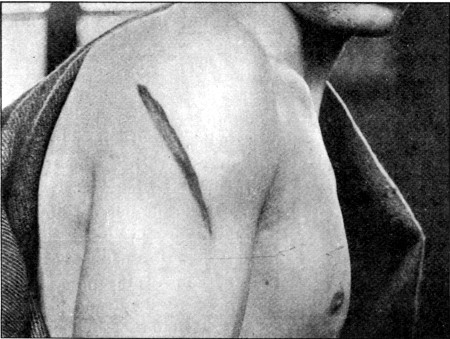

17. Gutter Wound of Shoulder56

18. Oblique Gutter Exit Wound 57